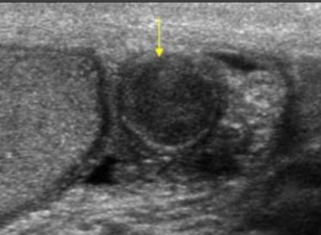

what component of the testis makes them appear as echogenic

seminiferous tubules

the testis are covered by the...

tunica albuginea

mediastinum testis

posterior aspect of tunica albuginea that forms vertical septum